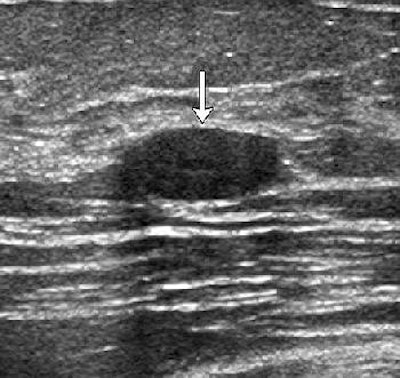

| Transverse images of fibroadenoma obtained in a 35-year-old woman during (a) conventional US and (b) tissue harmonic imaging. (a) A 1.0-cm oval-shaped slightly hypoechoic mass (arrow) is seen. (b) The mass (arrow) appears more hypoechoic and the circumscribed margin is clearly delineated. The final assessment by all readers was "probably benign" at both conventional US and tissue harmonic imaging. |

| Figure 4. Cha JH, Moon WK, Cho N, et al. "Characterization of benign and malignant solid breast masses: Comparison of conventional US and tissue harmonic imaging." Radiology 2007: 242(1): 63-69. |